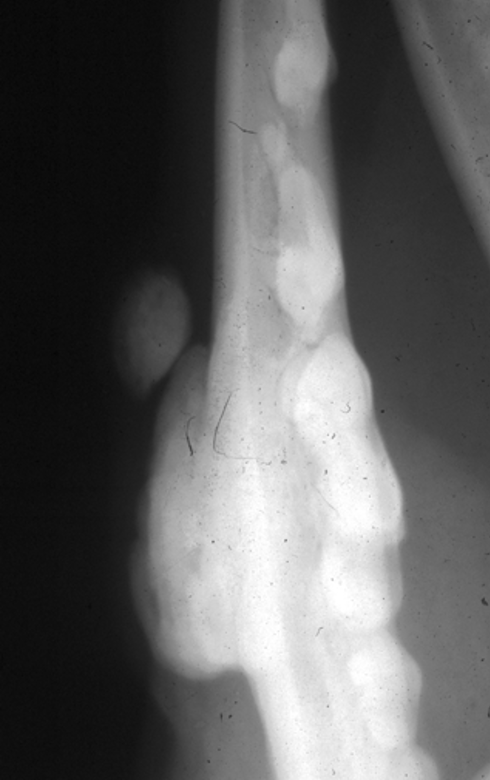

What is shown in this image?

A

osteosarcoma:

-ill-defined periosteal reaction

-soft tissue swelling